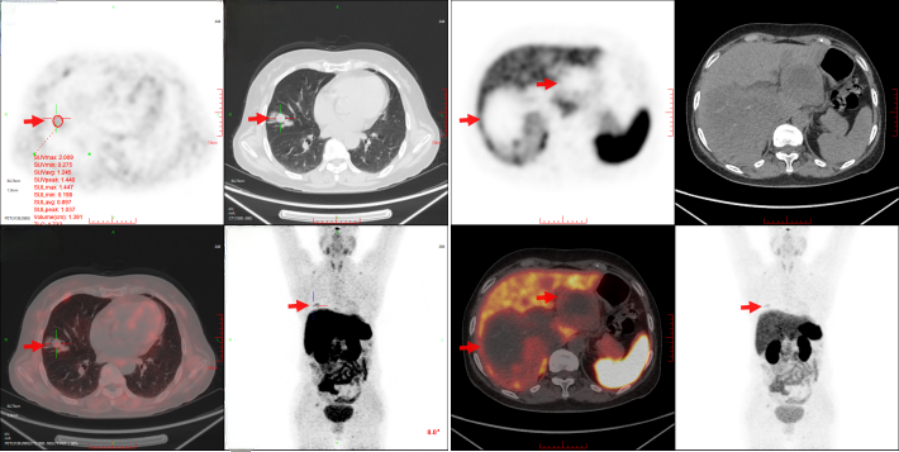

5)68Ga-DOTATATE(2023/1/16)

右肺中叶外侧段见一不规则软组织结节影,大小约1.5cm×1.3cm,边缘可见短毛刺影,SUVmax值为2.2,周围见模糊斑片影,邻近偏上方肺内另见一软组织结节影,大小约2.0cm×1.3cm,SUVmax值为3.0,符合神经内分泌肿瘤表现;肝内多发稍低密度肿块影、结节影,较大病灶位于右叶,大小约10.3cm×8.5cm,其内见稍高密度斑片影,显像剂分布不均;颅底骨、多发椎体及附件、双侧肩胛骨、右侧第4肋、右侧第8肋、右侧髂骨、左侧髋臼可见骨质破坏影,显像剂浓聚,SUVmax值为5.0(图2)。

图2 患者68Ga-DOTATATE PET/CT图像